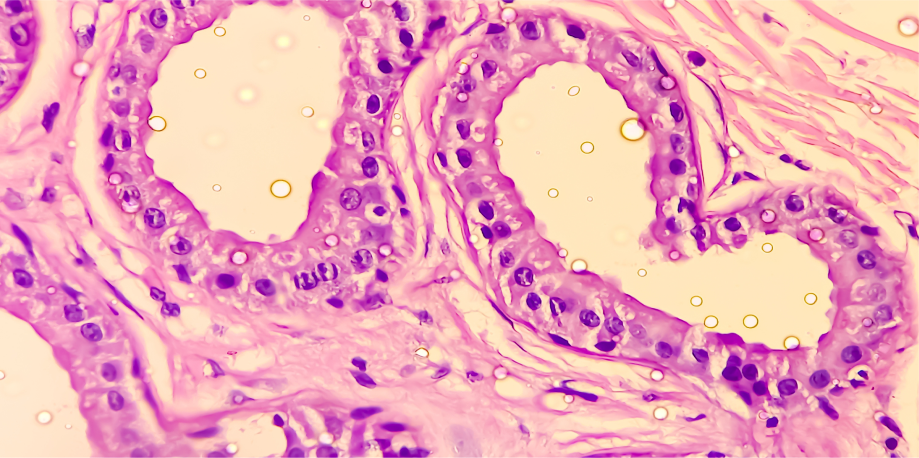

Estos factores hacen que los folículos pilosos (pelos) asociados a las glándulas apocrinas se obstruyan, lo que provoca la acumulación en su interior de diversas sustancias. Como consecuencia, los folículos pilosos se dilatan hasta romperse, y al liberarse el contenido acumulado se genera una respuesta inflamatoria. La inflamación es la responsable de los síntomas de la enfermedad.

La inflamación puede hacer que los folículos pilosos se bloqueen y aumenten de tamaño.

Los folículos pilosos obstruidos y dilatados pueden romperse, provocando bultos dolorosos, nódulos y abscesos.